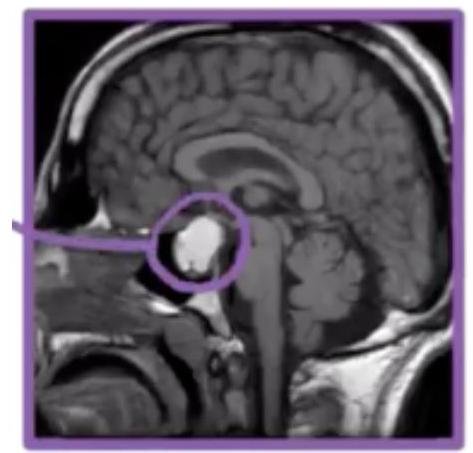

# HIPERPROLACTINEMIA ## DEFINICIÓN La **hiperprolactinemia** es una de las alteraciones hipotálamo-hipofisarias más comunes de la práctica clínica endocrinológica. Su importancia clínica está relacionada con su efecto sobre la función gonadal y mamaria, que causa infertilidad anovulatoria, trastornos menstruales, disfunción eréctil, acné, galactorrea y ginecomastia. Entre sus consecuencias a largo plazo, destaca la alteración de la densidad ósea y su posible asociación con enfermedades autoinmunes. ## FISIOLOGÍA **Hiperprolactinemia fisiológica**: **embarazo**, **lactancia**, **estimulación** pared **tórax**, **sueño, estrés**.  ## LESIÓN HIPOTÁLAMO/HIPÓFISIS: ## Tumores: Craneofaringioma, meningioma, disgerminoma, metástasis. ## Otros Silla turca vacía, hipófisis linfocitaria, adenoma con compresión del tallo, granulomas, quistes de Rathke, radiación. ## Traumatismo Sección del tallo hipofisario, cirugía supraselar. ## Trastornos sistémicos IRC, hipotiroidismo, cirrosis, crisis comiciales. Hipersecreción Hipofisaria: Prolactinoma, acromegalia. ## Fármacos: Antidepresivos, metoclopramida, domperidona, haloperidol, cimetidina, ranitidina, verapamilo. # CLÍNICA ## MUJERES - Anomalías del ciclo menstrual (oligomenorrea, infertilidad por ciclos anovulatorios, amenorrea). - Galactorrea se observa en 30-90% de las mujeres con hiperprolactinemia. ## HOMBRES - Disminución de la libido, impotencia e infertilidad. - El hipogonadismo es por inhibición de la liberación hipotalámica de GnRH. ## DIAGNÓSTICO No se necesita biopsia: es bioquímico y por imagen. | Mujer | Hombre | | :-- | :-- | | Menos de 20-25 ug/L | Menos 15-20 ug/L | La prolactina se eleva en el embarazo, alcanza pico en el parto. Valores máximos → 100 y 300 ug / L **PRL - 100** → **asociado** a **microadenoma**, **lesiones de tallo** e **hipotálamo**. **PRL 100-250** - pensar en un **microprolactinoma**. **PRL +250** → **sugerente** de **adenoma hipofisario productor de prolactina**, casi siempre **macroadenoma**. Se sugieren estudios de imagen (resonancia magnética) en hiperprolactinemia inexplicada, para encontrar lesiones en hipotálamo e hipófisis. - En la hiperprolactinemia idiopática puede haber anomalías que no se detecten mediante imagen, lo cual puede sugerir microadenoma oculto. ## DX DIFERENCIAL: HIPOTIROIDISMO, LA TRH TIENE EFECTO SOBRE EL GALATOTROPO. ## PROLACTINOMAS **Microadenoma** → **-10 mm** el más frecuente de todos y **predomina en mujeres**. **Macroadenoma** → **+10 mm** → **predomina en hombres**. Diagnóstico tardío por poca clínica hasta que esté avanzada.  # TRATAMIENTO Está indicado en las siguientes situaciones: 1. **Efecto de masa**: déficit de otras hormonas, defectos visuales, afectación nervios craneales, cefalea. 2. **Efecto hiperprolactinemia**: hipogonadismo, oligomenorrea, disfunción eréctil, osteoporosis. 3. **Relativas**: Hirsutismo, galactorrea. Agonistas dopaminérgicos clásicos: la **Bromocriptina** es un derivado ergotamínico con efecto dopaminérgico. Se inicia de forma progresiva para reducir los efectos colaterales (náusea, vómito). Agonistas dopaminérgicos modernos: **Quinagolida** y **Cabergolina**. Menos efectos secundarios y mejor eficacia. ## Retirada del tratamiento: - En pacientes que muestran reducciones en niveles de PRL y desaparición del adenoma o resultados importantes posterior a al menos dos años de tratamiento. - No son candidatos quienes no hayan reducido su tamaño o que el tumor no redujo al menos 50%. ## QUIRÚRGICO - La cirugía es necesaria en pacientes con defectos visuales persistentes a pesar de tratamiento, no toleran a los agonistas dopaminérgicos. - La cirugía - intervención transesfenoidal. - La morbimortalidad es mínima, aunque existen recidivas en un 40 %.